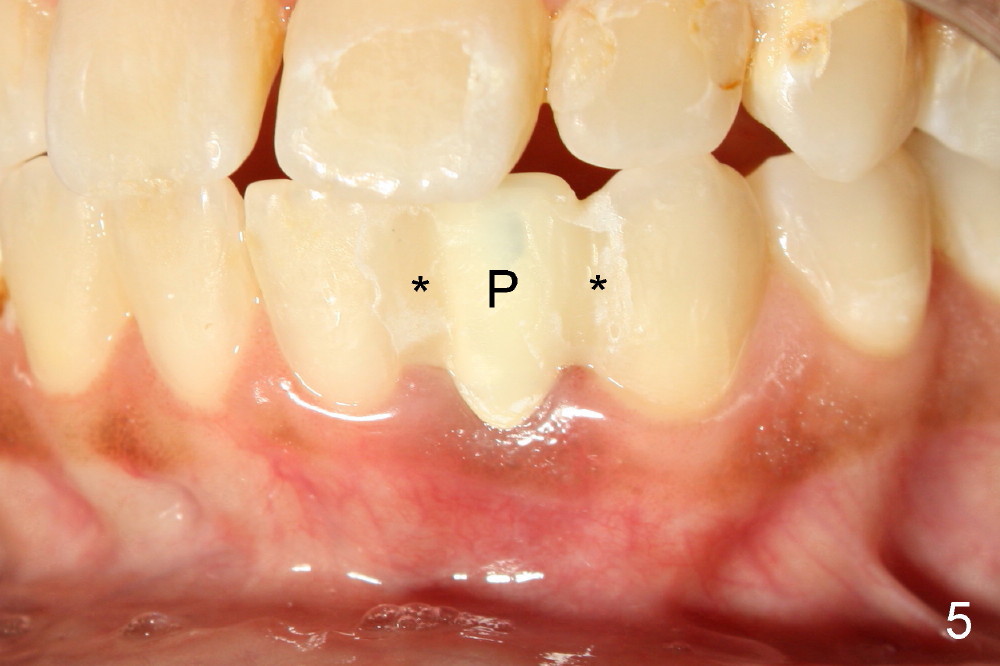

Informed consent is obtained with emphasis of potential damage to the neighboring roots. Two PAs have to be taken with the first pilot drill (1.5 mm) in place for determination of initial trajectory (Fig.2,3). Osteotomy is enlarged coronally with 2 mm pilot drill. Finally a 3x17 mm one piece implant is placed with primary stability, determined tactilely (Fig.4). Immediate provisional is fabricated. To avoid micromovement, the immediate provisional (Fig.5 P) is bonded to the neighboring teeth with composite (*); it is further fixed in place with a lingual retainer (Fig.6 arrowhead).